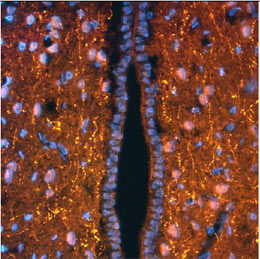

Immunohistochemical detection of ACTH in rat hypothalamus. Rat brain was fixed with 4% formaldehyde and cut into 10 μm thick cryostat sections. Tissue was incubated with rabbit polyclonal antibody to ACTH at 5 μg/mL overnight at 4°C followed by incubation with Donkey anti-rabbit Rhodamine Red conjugated secondary antibodies at 1:200. Tissue was counterstained with DAPI (blue color) to visualize cell nuclei.